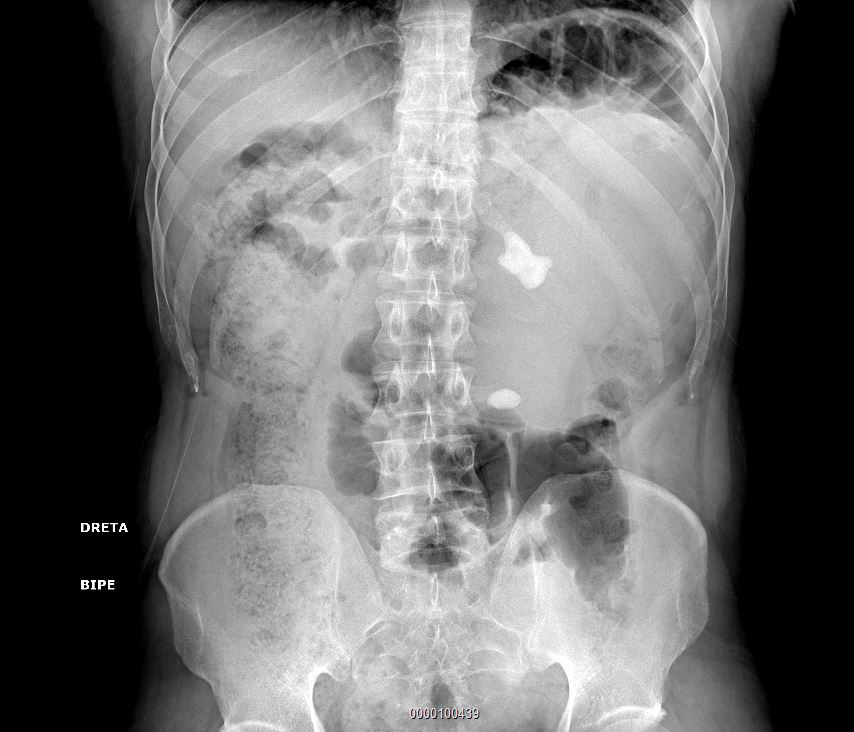

Ante el dolor lumbar persistente, se realiza radiografía de columna lumbosacra, sin alteraciones óseas, pero donde se describe una posible litiasis coraliforme en riñón izquierdo. Se cita al paciente para una ecografía clínica (EcoAP) de vías urinarias para completar el estudio.

Se evidencia riñón izquierdo con hidronefrosis grado 4+, completamente desestructurado que impiden reconocer arquitectura renal normal, con múltiples imágenes anecoicas, aumentado de tamaño llegando a sobrepasar línea media. Destaca una imagen hiperecogénica con múltiples sombras acústicas posteriores, compatible con litiasis coraliforme, en concordancia con la radiografía.

Las litiasis coraliformes representan entre el 2–20% de las litiasis renales y suelen formarse a partir de estruvita, asociadas a infecciones urinarias por bacterias productoras de ureasa (Proteus, Klebsiella, Pseudomonas) que alcalinizan la orina y favorecen un crecimiento rápido capaz de ocupar la pelvis y los cálices renales, lo que conlleva riesgo de uropatía obstructiva crónica y deterioro progresivo de la función renal.